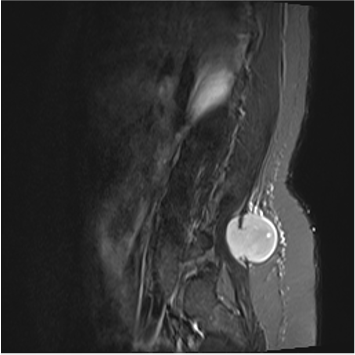

When Myeloma Extends Beyond the Bone Marrow: A Rare Pulmonary Manifestation

Rita Moreira, Sofia Rodrigues de Carvalho, Filipe da Cunha Pinto, Júlio Daniel Pacheco, Mariana Santos Freitas, Ana Areia Reis, Diana Pereira Anjos